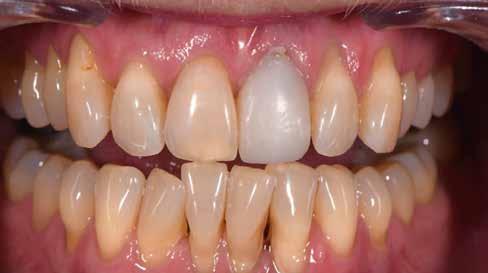

A 64 éves hölgypáciens esztétikus pótlást kívánt 21-es foga helyén, amelyet balesetet követően 2022-ben távolítottak el. Az összes foga egészséges és vitális volt, így a 21-es régióba implantátum került, amelyre cirkónium-dioxid koronát terveztünk. Az implantátum típusát, pozícióját, átmérőjét egyedi anatómiai adottságainak és az adott helyviszonyoknak megfelelően választottuk meg.

enyhén anémiás (vérszegény – a ford.), de gyorsan újra telítődik, tökéletesen illeszkedve a szituációhoz (36–42. képek)

A páciens a DD cube One koronát választotta, ami szín és transzparencia szempontjából is nagyon harmonikusan illeszkedett a teljes képhez (43–44. képek)